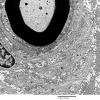

PERIPHERAL NEUROPATHY

20 PSEUDO-ONION BULBS (5)